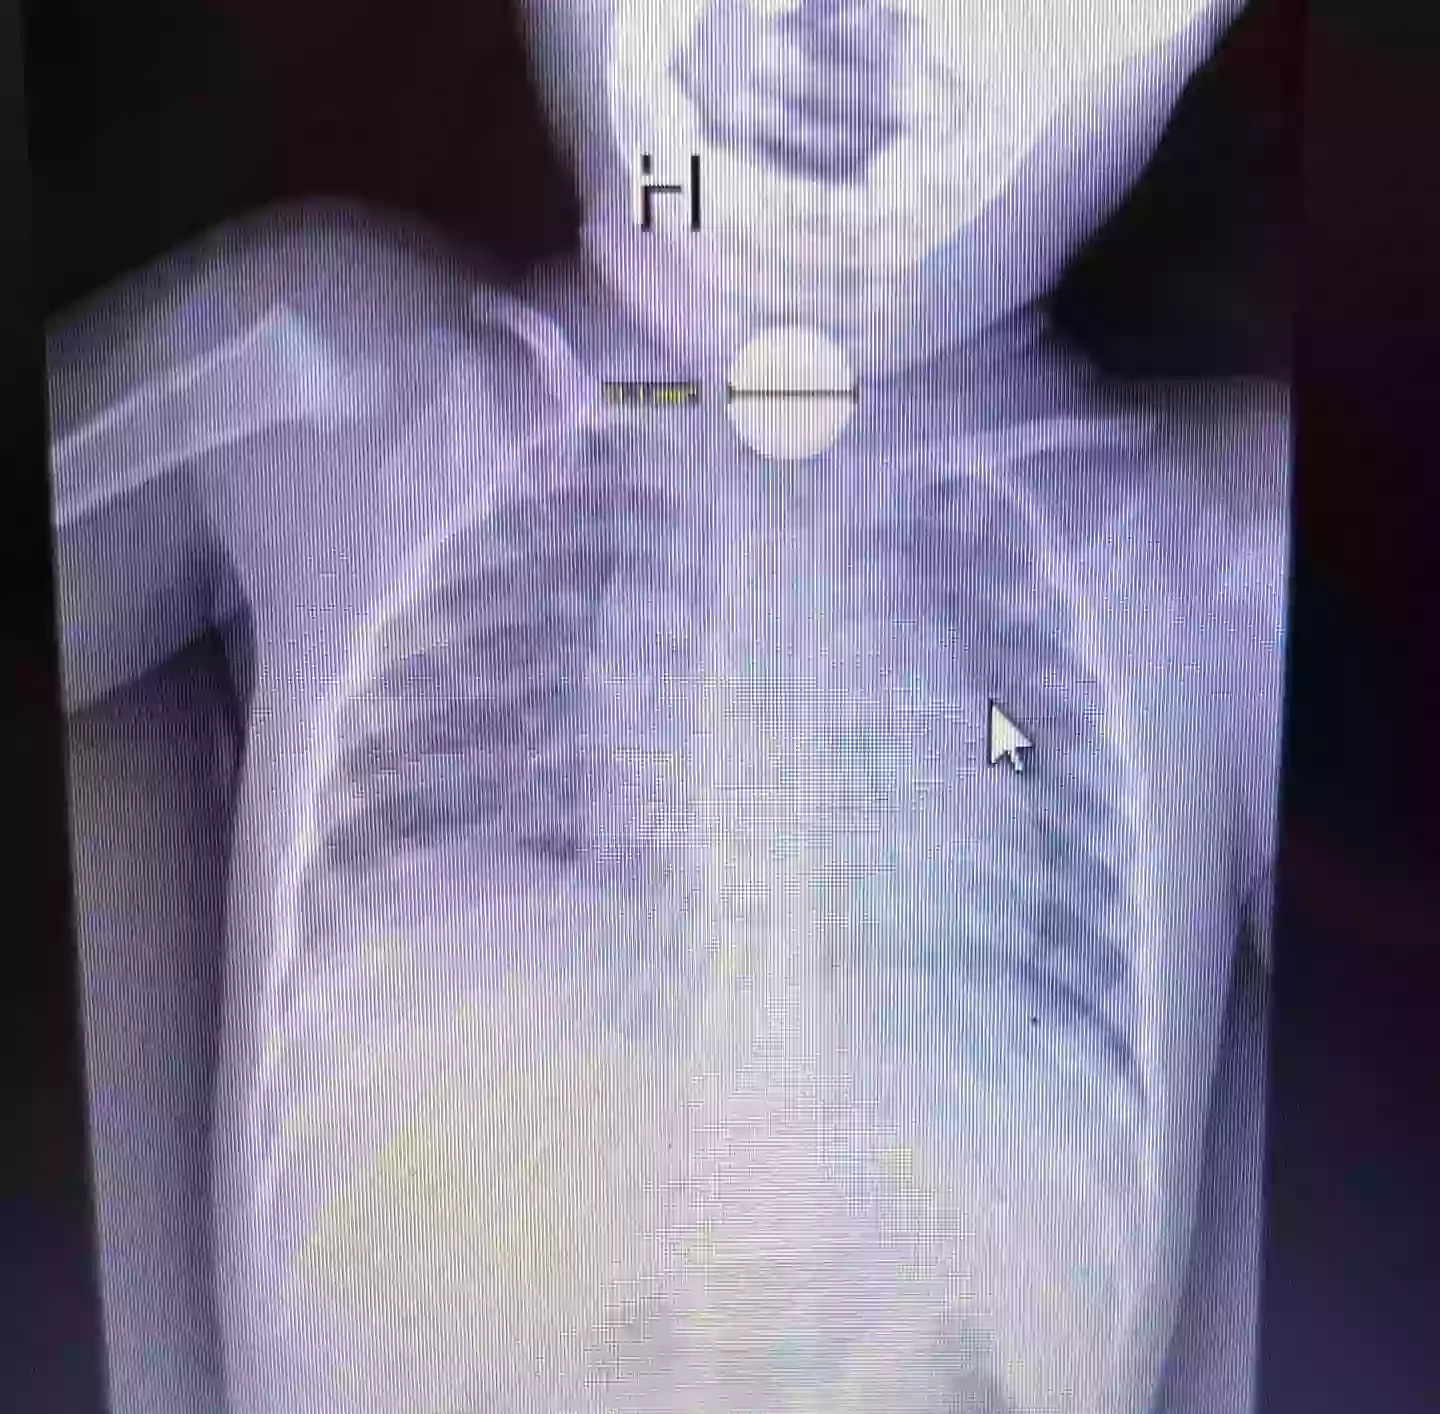

However, Madeline believed that it was something far worse and after pushing for an X-ray scan, it was revealed that Kai had swallowed a button battery which was burning its way through his throat.

Kai had swallowed a button battery that was burning its way through his throat (Kennedy News and Media)

“When we were walking back to the room there was already a team of doctors waiting in the room with him and they had the x-ray pulled up which showed the button battery in his throat.

An X-ray discovered the button battery (Kennedy News and Media)